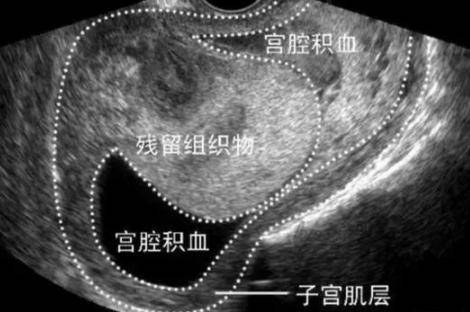

1、组织物残留。

可能因为妊娠月分较大,或子宫畸形、子宫肌瘤等原因,也可能因为手术操作者技术不熟练,致使妊娠组织物未完全清除,导致部分组织物残留于宫腔内。此时除了恶露不净,还有出血量时多时少,内夹血块,并伴有阵阵腹痛。